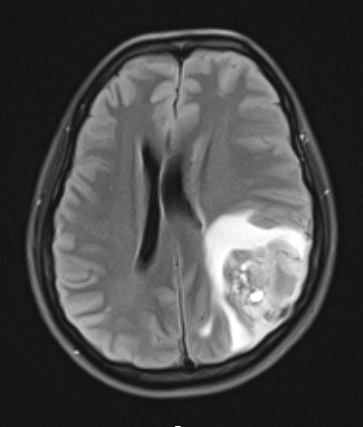

Case 22 History ---- The patient is a 27-year-old woman presenting with two weeks of headaches and a cystic, enhancing mass in the left parieto-temporal region. Operative procedure: left craniotomy for tumor resection with fluorescein, spinal cord monitoring. ---- 22A1 The tumor is a hyperintense mass in the left parieto-temporal lobe with adjacent edema as seen in a FLAIR scan.